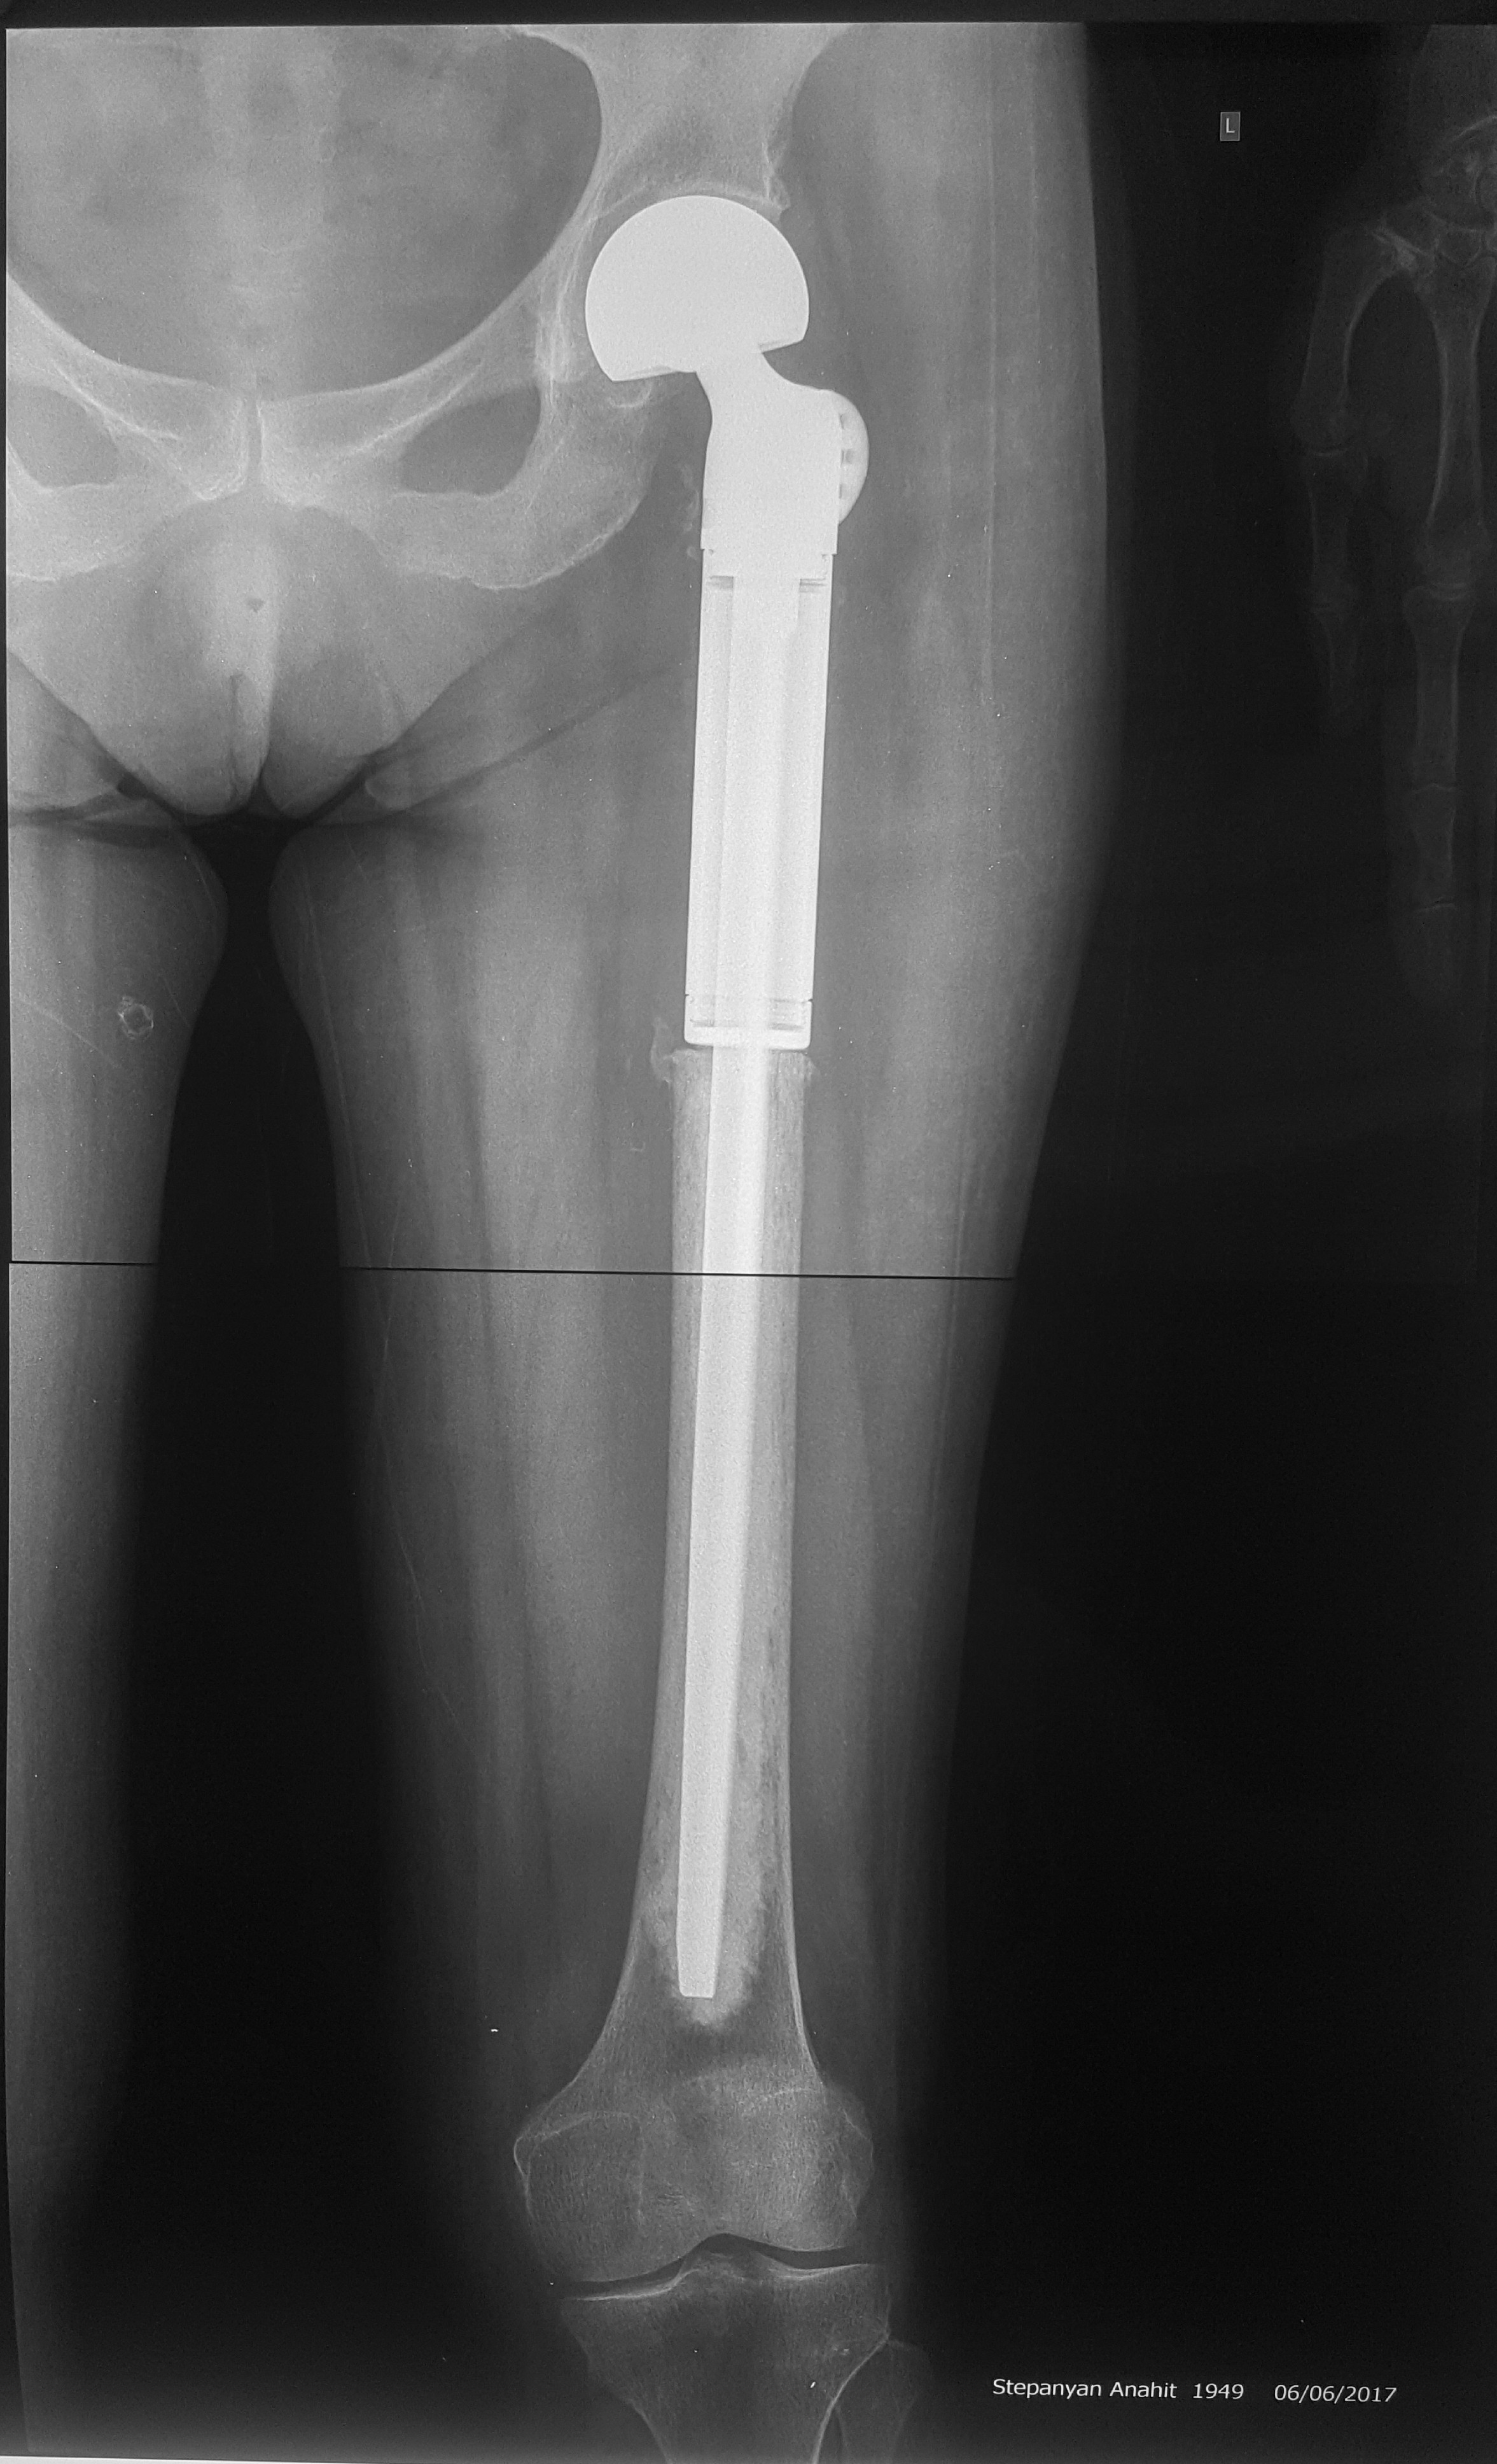

2. Բժշկական տարբեր կենտրոններում հետազոտվելուց հետո՝ 17-ամյա պատանին դիմել է «Նաիրի» ԲԿ։ Համապատասխան հետազոտություններ անցնելուց հետո՝ բուժառուի մոտ հայտնաբերվել է ոլոքի օստեոսարկոմա (ոսկրային քաղցկեղ): Նախավիրահատական բուժում ՝ քիմիոթերապիա, ստանալուց հետո՝ «Նաիրի» ԲԿ ում կատարվել է օրգանապահպան վիրահատություն : Հեռացվել են ծնկահոդն ու ոլոքի վերին երորդականը: Առաջացած դեֆորմացիան շտկել է Եվրոպայից պատվիրված էդոպրոթեզով, որը հնարավորություն է տվել պահպանել վերջույթի գործառույթը՝ քայլել, վազել և այլն։ Հետվիրահատական շրջանում բուժառուն ստացել է քիմիոթերապիա։ Այժմ գտնվում է բժիշկների հսկողության ներքո։

Վիրահատությունից առաջ

Վիրահատությունից հետո